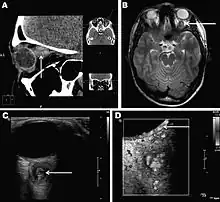

Infections in humans[2] usually manifest as a single subcutaneous nodule, which is caused by a macrofilaria that is trapped by the immune system. Subcutaneous migration of the worm may result in local swellings with changing localization. In addition, rare cases of organ manifestation have been reported, affecting the lung, male genitals, female breast, or the eye. The latter is found in particular during the migratory phase of the parasite. D. repens occurs more commonly in adults (aged 40–49 years). The only exception is in Sri Lanka, where children younger than nine years are most likely to be infected. The youngest individual reported was aged four months.[3]

Final diagnosis is established by microscopic examination of the excised worm. Making a definite species diagnosis on morphologic grounds is difficult, because a large number of zoonotic Dirofilaria species have been described that share morphologic features with D. repens.

- ↑ Sven Poppert, Maike Hodapp, Andreas Krueger, Guido Hegasy, Wolf-Dirk Niesen, Winfried V. Kern, and Egbert Tannich (November 2009). "Dirofilaria repens Infection and Concomitant Meningoencephalitis". Emerg. Infect. Dis. 15 (11): 1844–1846. doi:10.3201/eid1511.090936. PMC 2857255. PMID 19891881.